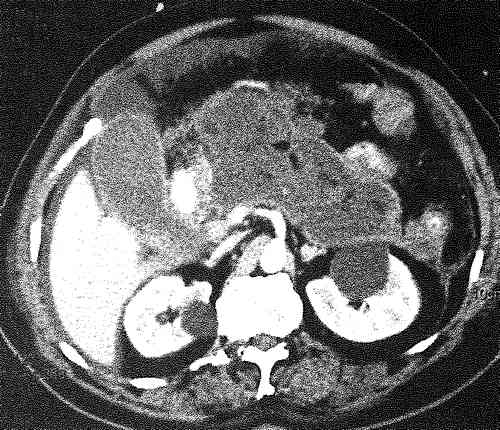

- КТ и МРТ поджелудочной железы детально визуализирует патологические изменения, помогает с высокой точностью установить локализацию некроза.

- Визуализация тесты, которые могут включать УЗИ брюшной полости или компьютерную томографию

Ваш поставщик медицинских услуг исключит другие причины ваших симптомов. Они проверят вас за язва, воспаление желчного пузыря или рак поджелудочной железы. Ваше здравоохранение Медицинский работник часто может диагностировать НП с помощью другого метода визуализации, например МРТ.

- Это состояние часто диагностируется с помощью КТ или другого метода визуализации.

Острый некротизирующий панкреатит — тяжелая форма острого панкреатита, характеризующаяся некрозом в поджелудочной железе и вокруг нее и связанная с высокими показателями заболеваемости и смертности. Хотя острый интерстициальный отечный панкреатит диагностируется в первую очередь на основании признаков, симптомов и результатов лабораторных исследований, диагностика и оценка тяжести острого некротического панкреатита в значительной степени основываются на данных визуализации. На основании пересмотренной системы классификации Атланты 2012 г. некротизирующий панкреатит анатомически подразделяется на паренхиматозный, перипанкреатический и комбинированный подтипы, а по времени — на раннюю клиническую (в течение 1 недели от начала) и позднюю (> 1 недели после начала) фазы.

Связанные коллекции классифицируются как «острые некротические» или «отгороженные» и могут быть стерильными или инфицированными. Визуализация, в первую очередь компьютерная томография и магнитно-резонансная томография, играет важную роль в диагностике некротизирующего панкреатита и выявлении осложнений, включая инфекцию, обструкцию кишечника и желчевыводящих путей, кровотечение, формирование псевдоаневризмы и венозный тромбоз. Визуализация также используется для помощи в сортировке пациентов, а также для временного и окончательного лечения. Было показано, что «ступенчатый» метод лечения некротизирующего панкреатита, в котором используется чрескожный катетерный дренирование скоплений жидкости под контролем визуализации перед эндоскопической или хирургической некрэктомией, улучшает клинические результаты. Авторы представляют алгоритмический подход к лечению пациентов с некротизирующим панкреатитом и рассматривают использование методов визуализации и интервенционных методов в диагностике и лечении этого патологического состояния.